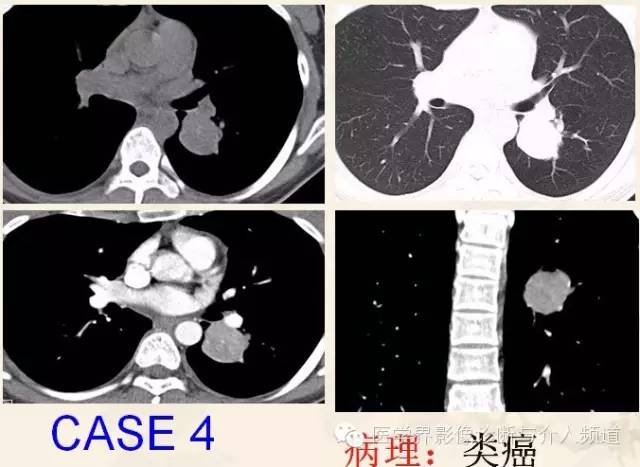

类癌(carcinoid)

又称嗜银细胞瘤(argentaffinoma),起源于神经内分泌细胞的肿瘤,能产胺、产肽,属于APUD细胞(amine precursor uptake decarboxylation)系统。

类癌是一种低度恶性神经内分泌肿瘤,约85%发生于胃肠道。按其组织学特点分为K细胞癌I型,即典型类癌和K细胞癌II型,即不典型类癌,该病病程缓慢,预后良好,能长期生存,目前认为支气管肺类癌属低度恶性肿瘤。

90%患者<50岁,主要表现为咳嗽、咯血及反复肺部感染。周围型患者多数无症状。 临床与CT表现

由于类癌内分泌潜能而分泌多种激素,可存在特殊临床症状,如皮肤潮红、腹泻、哮喘及心悸等(类癌综合征)。

支气管肺类癌密度大多较均匀,很少有液化、坏死及囊性变,空洞者也很少见。

文献报道组织学上支气管肺类癌钙化的发生率为30%,中央型支气管肺类癌可高达39%,钙化呈斑片状、偏心型或弥漫型。

肺类癌为富血供肿瘤,由气管动脉供血,故CT增强扫描时多呈明显或中度强化。